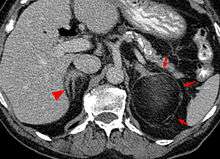

Most myelolipomas are unexpected findings on CT scans and MRI scans of the abdomen. They may sometimes be seen on a plain X-ray films.[6]

- 1 2 3 4 Ramchandani, P. Adrenal Myelolipoma Imaging at eMedicine